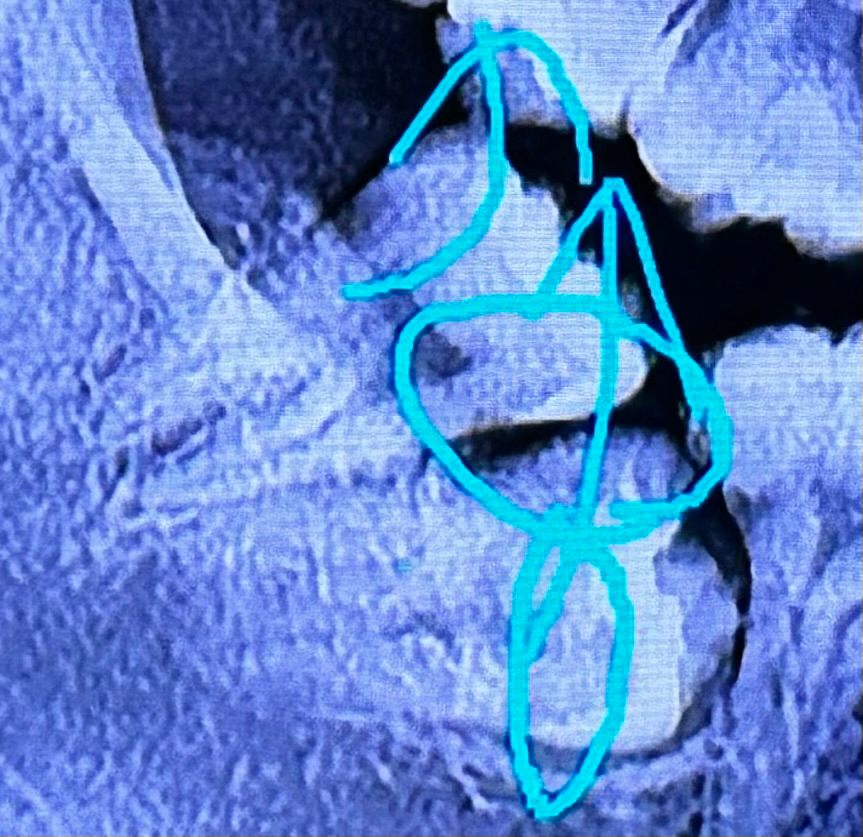

이런 치아도 이식술이 가능할까요?

사진에서 밖으로 자라있는게 사랑니고, 매복되어있는게 원래 어금니에요

이런 케이스가 흔치 않은것을 알지만... 두 치아를 다 뽑고 임플란트를 하기에는 20대 초반이라 솔직히 심리적으로 부담이 돼요 ㅠㅠ

찾아보니 자가 치아 이식술이라는데 있던데 이 시술도 뿌리가 곧게 자라있어야 가능한 시술인건가요...?

치아 상태는 둘다 좋아요